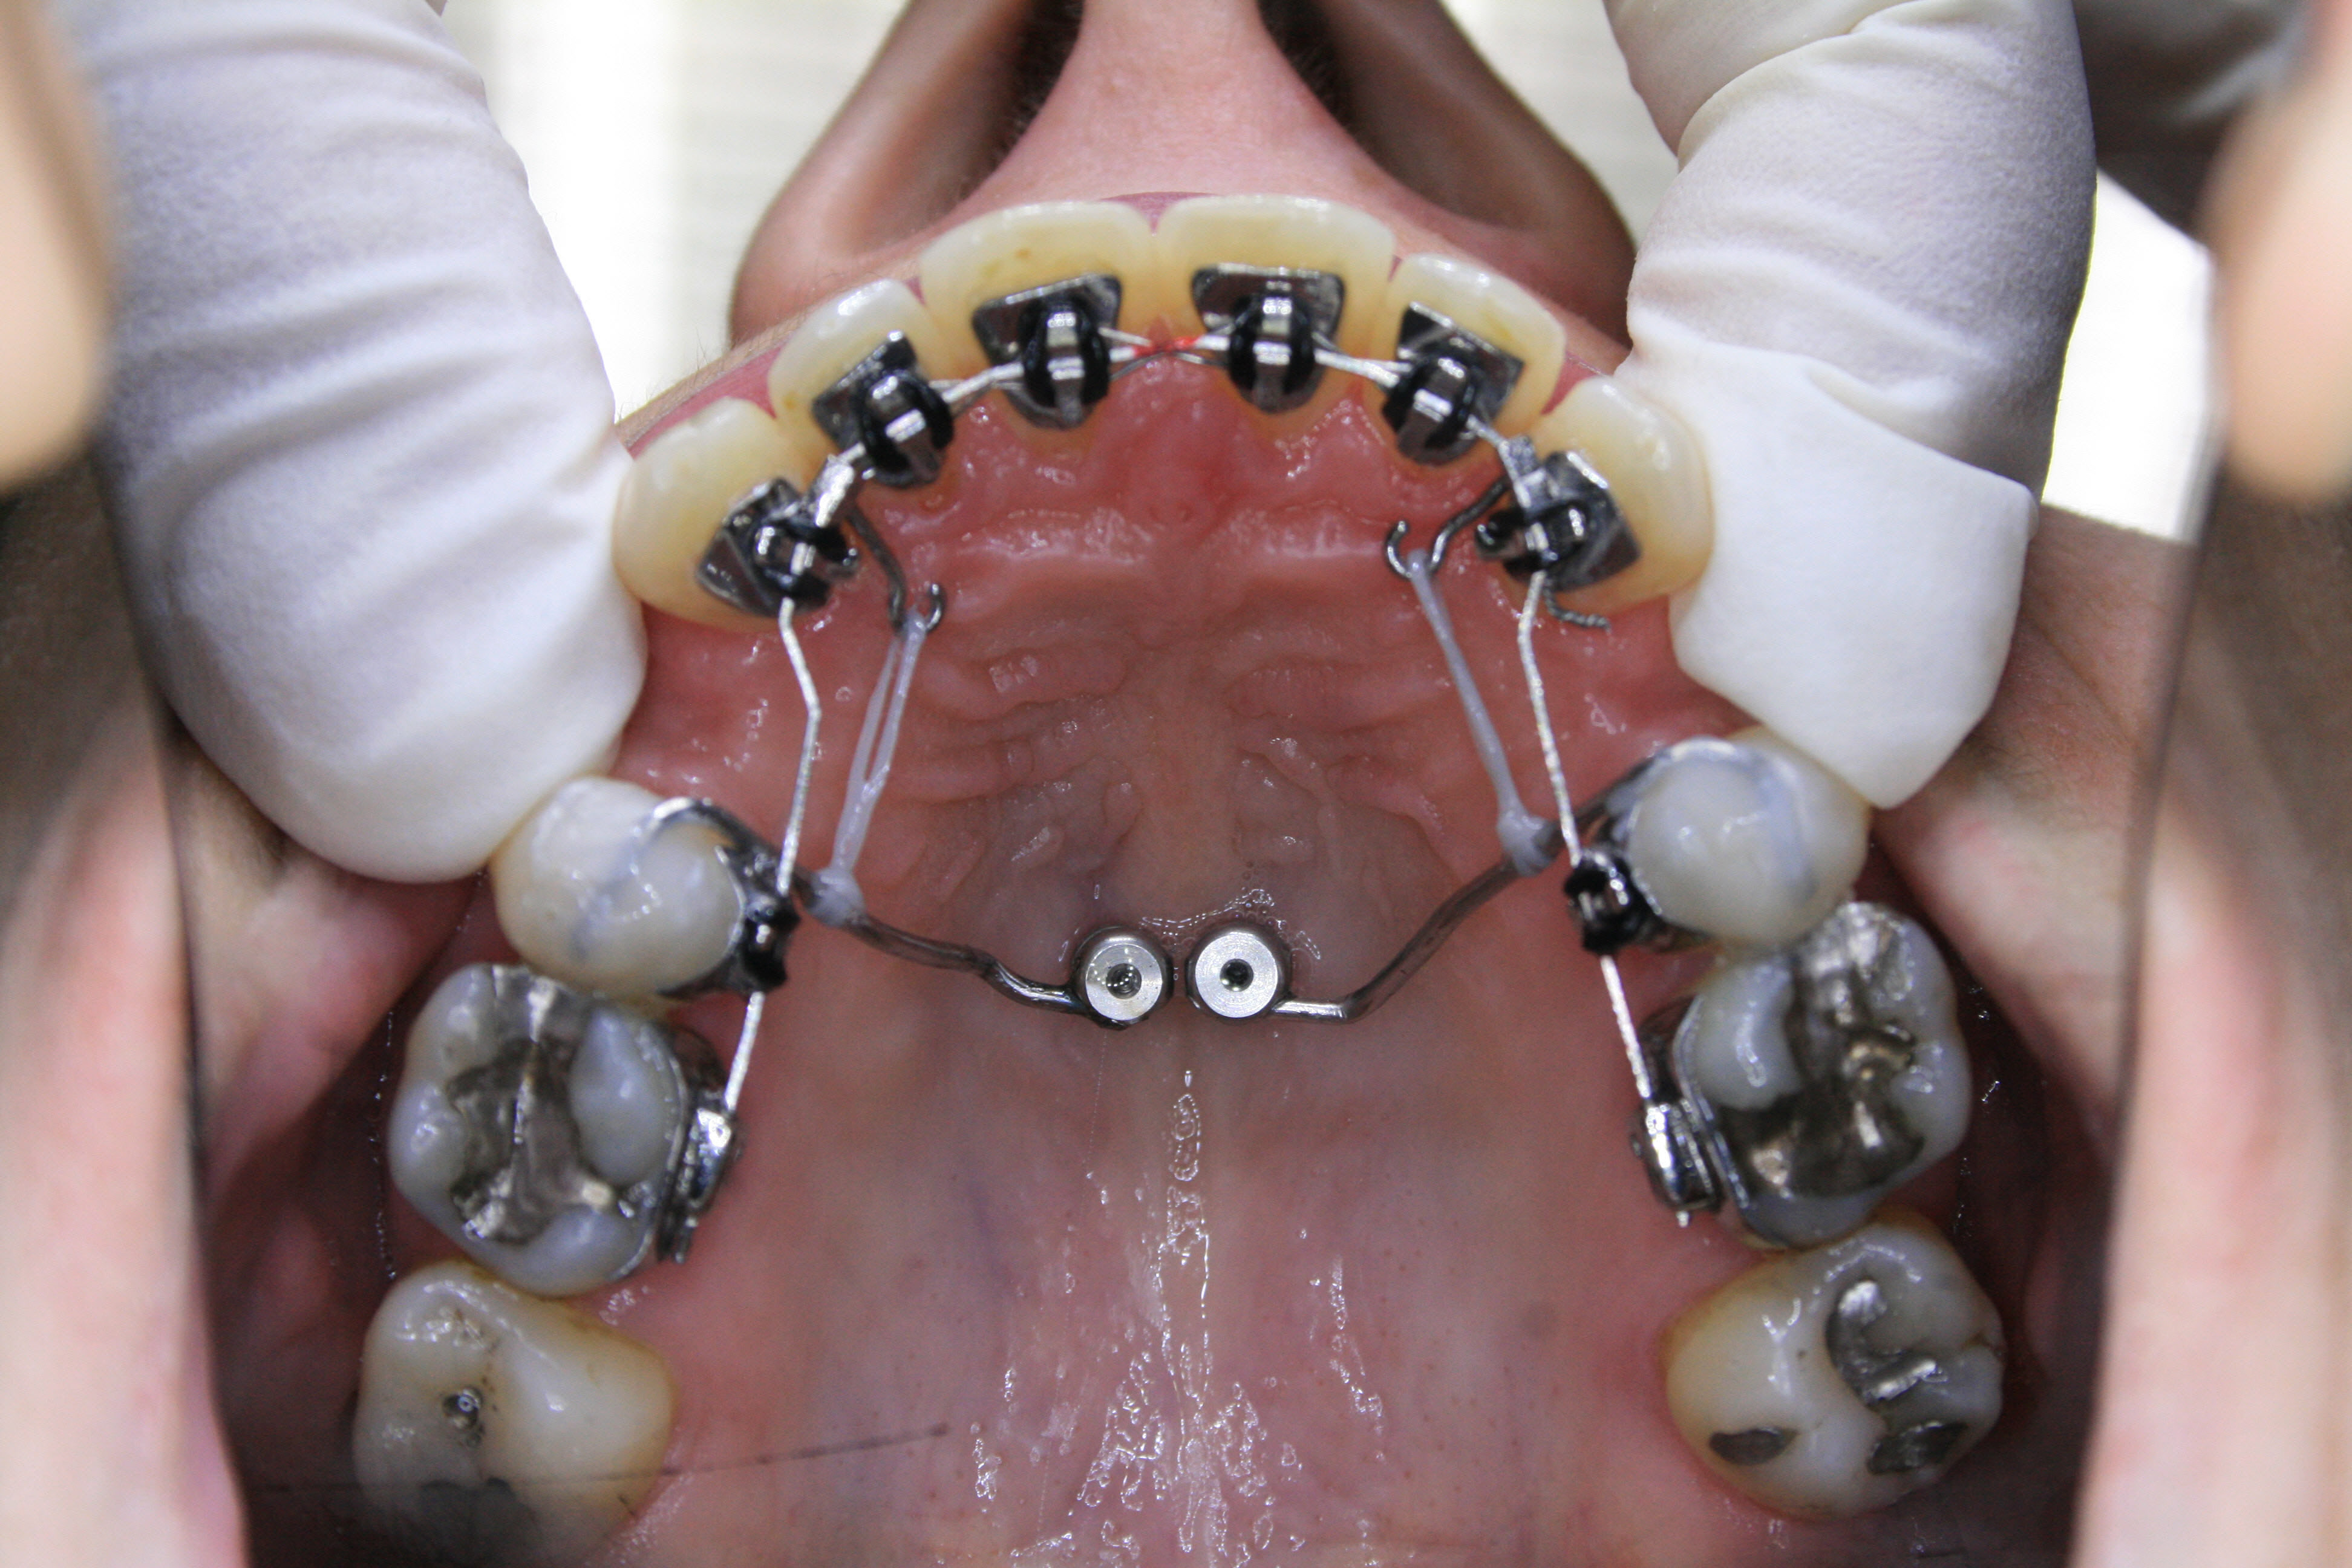

Während der Behandlung

Die ersten kleinen Backenzähne sind bereits entfernt und die festsitzende Zahnspange ist eingesetzt, in diesem Falle quasi unsichtbar auf der Innenseite der oberen Schneidezähne. Es ist wesentlich, daß die Lücken nur von vorne her geschlossen werden. Dies wurde sichergestellt, indem die Zähne hinter den Lücken über temporäre kleine Implantate am Gaumendach verankert wurden. In der Bildsequenz ist der Behandlungsfortschritt zu erkennen; der Lückenschluß war nach 1½ Jahren erreicht.